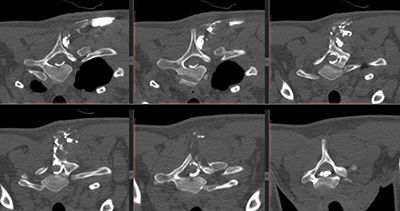

Медицинский термин «фистулография» используют для обозначения рентгеновского диагностического исследования, направленного на определение свищевых ходов посредством их заполнения рентгеноконтрастным веществом. Это необходимо для того, чтобы врач смог определить метод иссечения свища и разработал тактику последующего лечения заболевания, которое привело к его образованию.

Процедура имеет высокую диагностическую ценность, поскольку позволяет проводить обследование свищевых ходов, определять их направление, протяжённость, наличие затёков и полостей, а также выявлять связь со смежными структурами. После того, как свищевой ход заполнен контрастом, проводится съёмка рентгеновским аппаратом, которая позволяет зафиксировать необходимые данные.

Фистулография – это исследование, позволяющее определить локализацию, протяженность и особенности строения свища (фистула – это другое название данного образования). Для этого в патологический вход вводится контрастное вещество, а данные фиксируются посредством рентгеновского снимка. Знание показаний, преимуществ и описания процедуры позволит правильно подготовиться к ней.

В проктологии фистулографию используют для выявления и дифференциальной диагностики при заболеваниях аноректальной и крестцово-копчиковой областей при обнаружении на коже свищей.

Метод фистулографии очень эффективен для определения направления, протяженности, разветвлений свищевого хода, выявления образовавшихся по его ходу полостей и взаимоотношений с соседними органами.

Как проводится фистулография свища

Фистулография может проводиться как до операции, так и во время нее, или даже после оперативного вмешательства. Перед началом исследования проводятся рентгенограммы в двух перпендикулярных проекциях.

Во время фистулографии во внешнее свищевое отверстие вставляют иглу или катетер и вводят рентгеноконтрастное вещество. Это масляные или водные соединения йода (уротраст, омнипак, верографин, йодолипол, пропилйодон) или взвесь бария.

Объем вводимого вещества зависит от размера и глубины свища (главное правило: пространство должно быть заполнено доверху). Затем заполненное отверстие плотно прикрывают шариком из марли, заклеивают медицинским клеем или лейкопластырем и готовят несколько рентгенологических снимков в различных проекциях. После проведения фистулографии контрастное вещество удаляют, или оно вытекает самостоятельно. Иногда фистулографию делают под анестезией.